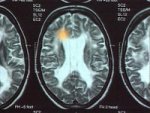

Brain damage through multiple sclerosis

In cases of autoimmune diseases such as multiple sclerosis, immune system's defences act against the body's own tissue.

In the case of multiple sclerosis, nerve pathways in the brain are attacked. Inflammatory rheumatism leads to destruction of the bone tissue.